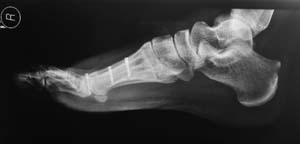

This is the x-ray finding:

A scarf osteotomy was performed. It involved cutting the 1st metatarsal bone using a Z-cut and displacing the toe laterally.